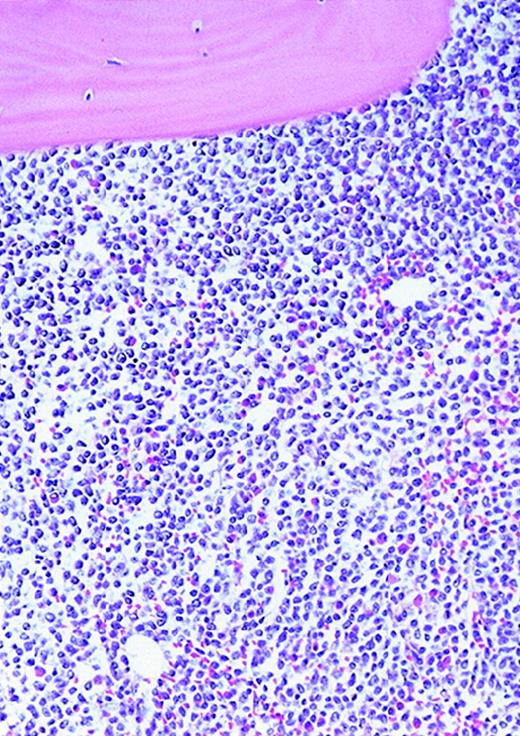

High-power view of vascularity of normal and AML marrow specimens.

Normal or AML bone marrow samples were stained for vWF expression (see Methods). A = 600× view of normal bone marrow showing positive staining in a megakaryocyte as well as 1 vessel. B = 400× view of representative AML marrow showing numerous vessels. Note that some of the vessels are large with irregular and bizarre shapes. C = 600× view of representative AML marrow showing details of vascular endothelial cell staining.